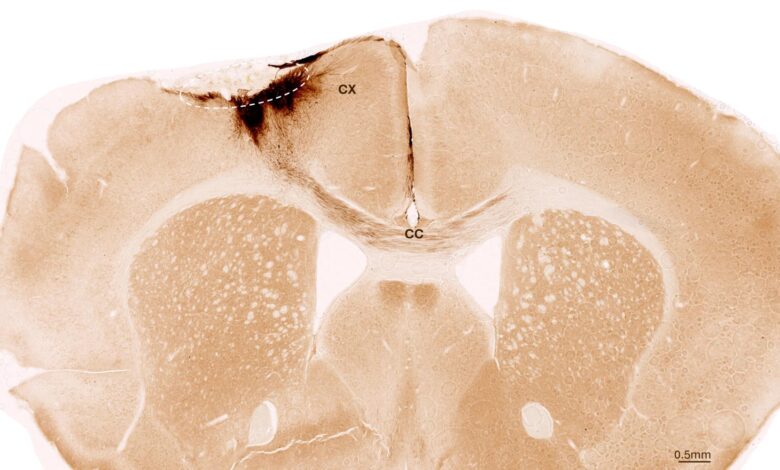

Studie používaly lidské nervové kmenové buňky, ze kterých se mohou tvořit různé typy buněk nervového systému. Kmenové buňky byly odvozeny z indukovaných pluripotentních kmenových buněk, které lze zase vyrobit z normálních lidských somatických buněk. Pro jejich zkoumání vědci vyvolali trvalou mrtvici u myší, jejichž charakteristiky se velmi podobají projevu mrtvice u lidí. Zvířata byla geneticky modifikována tak, aby neodmítla lidské kmenové buňky.

Jeden týden po indukci mrtvice výzkumný tým transplantoval nervové kmenové buňky do poškozené oblasti mozku a pozoroval následné vývoj pomocí různých zobrazovacích a biochemických metod. „Zjistili jsme, že kmenové buňky přežily po celou dobu analýzy po pěti týdnech a že většina z nich se transformovala na neurony, které dokonce dokonce komunikovaly s již existujícími mozkovými buňkami,“ říká Tackenberg.